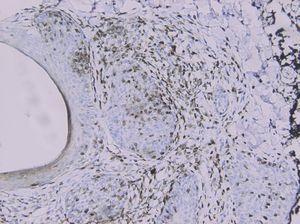

La histología mostraba una llamativa degeneración del epitelio folicular (fig. 2) con presencia de material mucinoso. A nivel perifolicular se observaba un infiltrado linfoide con cierto foliculotropismo y sin células atípicas. El estudio inmunohistoquímico mostraba una positividad para CD3 (fig. 3), sin un claro predominio CD4/CD8. Los marcadores B y el CD30 eran negativos. Mediante técnica de reacción en cadena de la polimerasa (PCR) no se puso de manifiesto un reordenamiento monoclonal del gen TCRγ.

Fig. 2.—H/Eo. Degeneración epitelio folicular. Infiltrado linfoide perianexial.